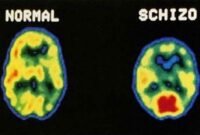

5 Penyakit yang Penderitanya Harus Minum Obat Seumur Hidup

sepanjang hidup. 1. Hipertensi Yaitu suatu kekuatan yang mendorong darah ke dinding bagian dalam arteri. Dampak dari hipertensi dapat meningkatkan …selangkapnya